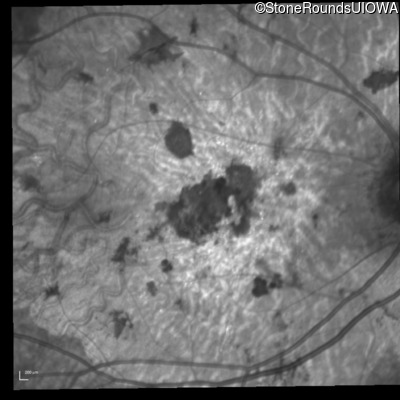

Blue Autofluorescence - Left - 20/300 sc

Exemplar